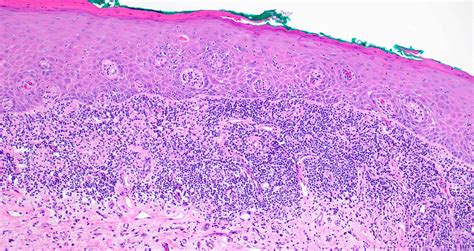

At its core, Erosive Lichen Planus is an autoimmune inflammatory condition. While the exact cause remains unknown, it occurs when the body's immune system mistakenly attacks the lining cells of the mucous membranes. This persistent inflammation leads to the breakdown of the tissue, resulting in painful, red, and eroded areas that are often rimmed with white, radiating lines known as Wickham striae. Because it is a chronic condition, patients often experience periods of remission followed by painful flares.

• Bright red patches: Areas where the outer layer of the mucosal lining has been shed.

• Ulcerations: Open, raw sores that bleed easily.

• White striae: Lacy, web-like white lines surrounding the red or ulcerated areas.

• Gingival involvement: Often manifesting as desquamative gingivitis, where the gum tissue appears raw and peels away.